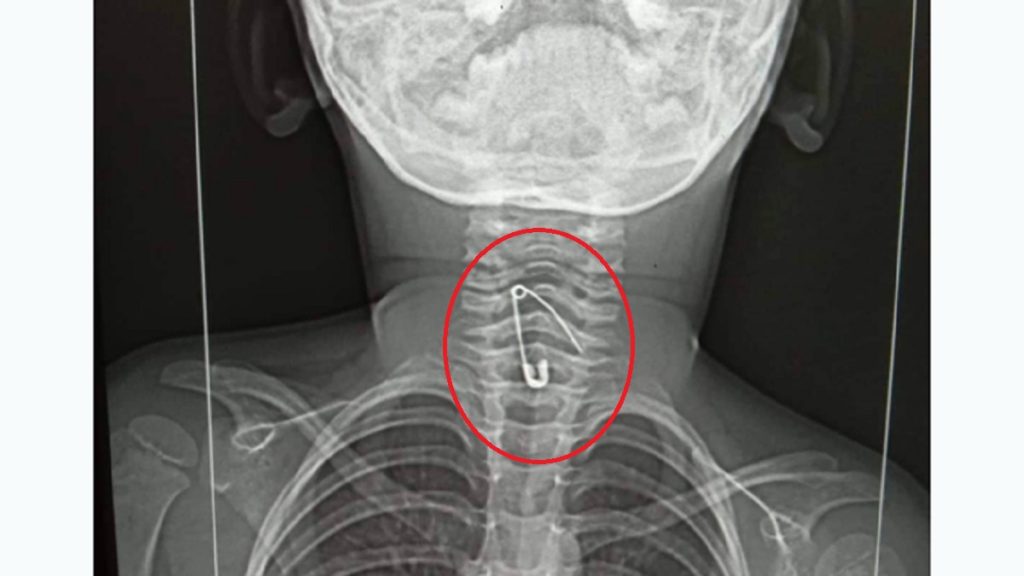

শফিকুল ইসলাম জানান, বুধবার (২৪ আগস্ট) দিবাগত রাত ১২টার দিকে জিদনি খাবে না বলে বায়না ধরে। এতে তার মা জুলেখা বেগম নানা ছলাকলায় খাওয়ানোর চেষ্টা করে। একপর্যায়ে শিশুটিকে মেঝেতে নামিয়ে খেলার ছলে নুডুলস খাওয়ায়। এর কিছুক্ষণের মধ্যে জিদনি বমি করতে শুরু করে। শিশুটি অসুস্থ হয়ে পড়লে তাকে বাঘা সেবা ক্লিনিকে ভর্তি করানো হয়। সেখানকার চিকিৎসকরা রাতেই তাকে রাজশাহী মেডিকেল কলেজ হাসপাতালে প্রেরণ করে। রাজশাহী মেডিকেল কলেজে ৩৩ নম্বর ওয়ার্ডে ভর্তির পর এক্সরে করানো হয়। দেখা যায়, গলায় আটকে আছে আস্ত সেফটিপিন।

ওই ওয়ার্ডের দায়িত্বরত চিকিৎসক জানিয়েছেন, রাজশাহী মেডিকেল কলেজ হাসপাতালে গলার ভেতর খেকে সেফটিপিন বের করার মতো চিকিৎসা সরঞ্জাম নেই। সে কারণে ঢাকা মেডিকেল কলেজ হাসপাতালে রেফার্ড করা হয়েছে। শুক্রবার দুপুরে পরিবারের লোকজন জিদনিকে নিয়ে ঢাকায় রওয়ানা হয়েছেন।